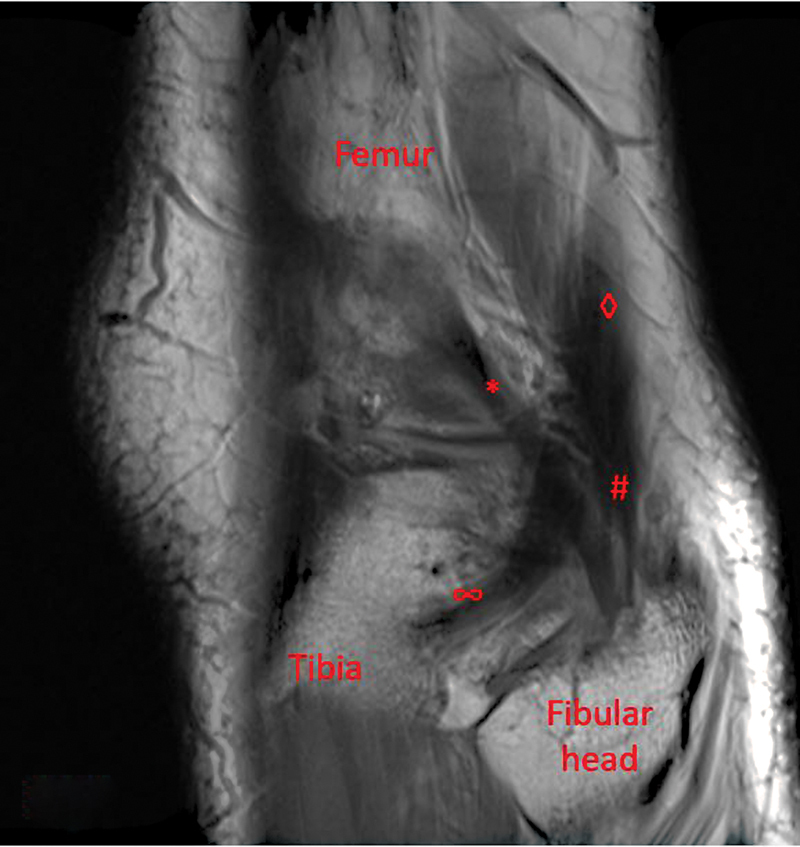

This case involves a healthy male with painful lateral knee pain and snapping after a hyperextension injury. Initially, this was felt to be from a displaced lateral meniscus tear; however, he failed to improve after meniscal debridement. Further workup with an ultrasound and magnetic resonance imaging identified an aberrant biceps femoris anatomy. He was taken to the operating room and the aberrant slip was identified. A tenodesis of the aberrant slip to the biceps femoris was completed. This resolved the patient's pain and snapping, and he was able to return to all activities.

Abstract Image